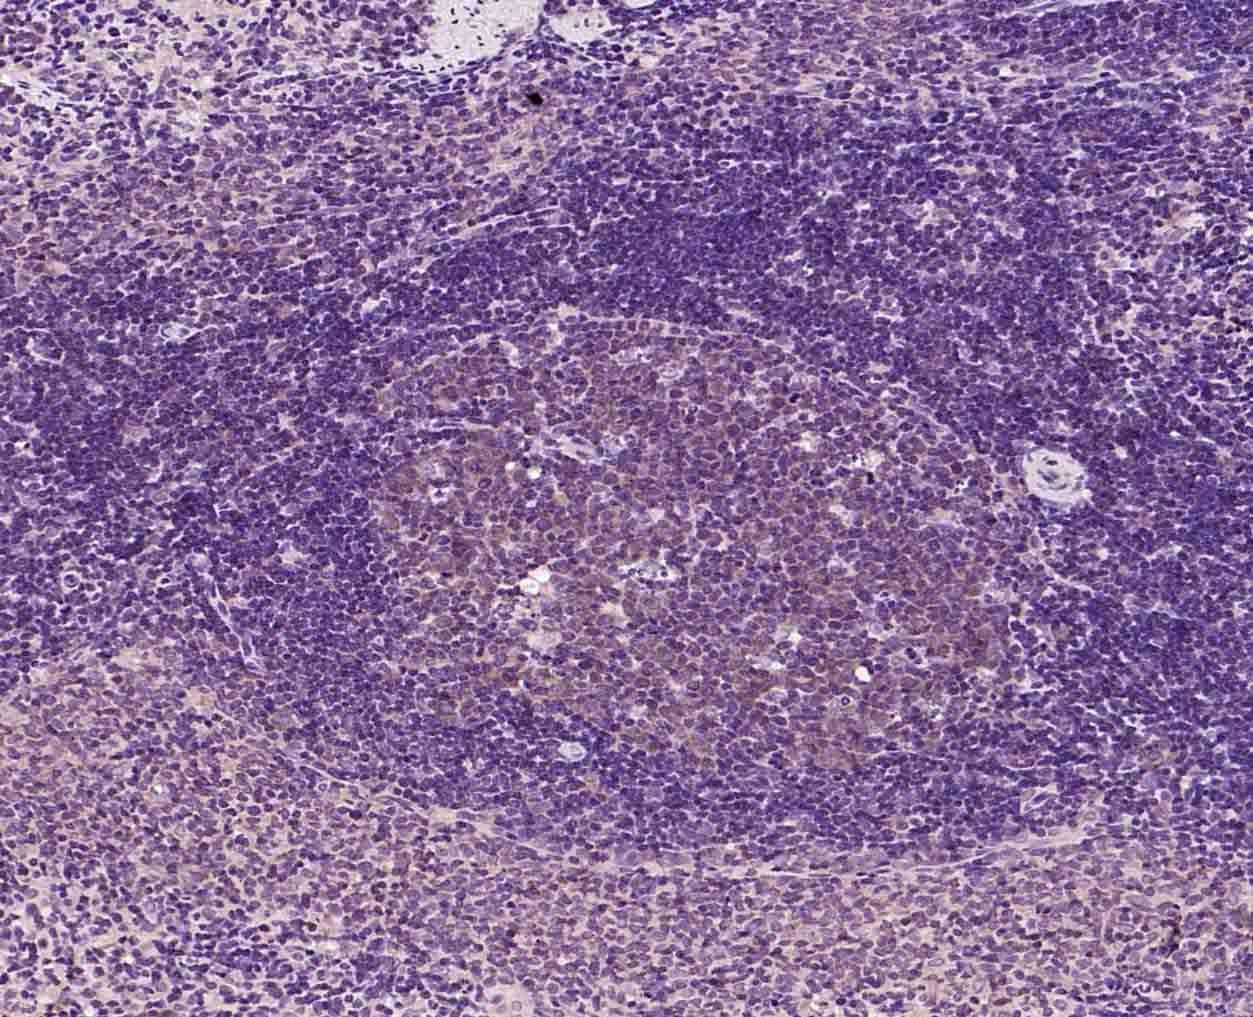

Paraformaldehyde-fixed, paraffin embedded (rat spleen); Antigen retrieval by boiling in sodium citrate buffer (pH6.0) for 15min; Block endogenous peroxidase by 3% hydrogen peroxide for 20 minutes; Blocking buffer (normal goat serum) at 37°C for 30min; Incubation with (PIBF1) Polyclonal Antibody, Unconjugated (bs-9612R) at 1:200 overnight at 4°C, followed by operating according to SP Kit(Rabbit) (sp-0023) instructionsand DAB staining.